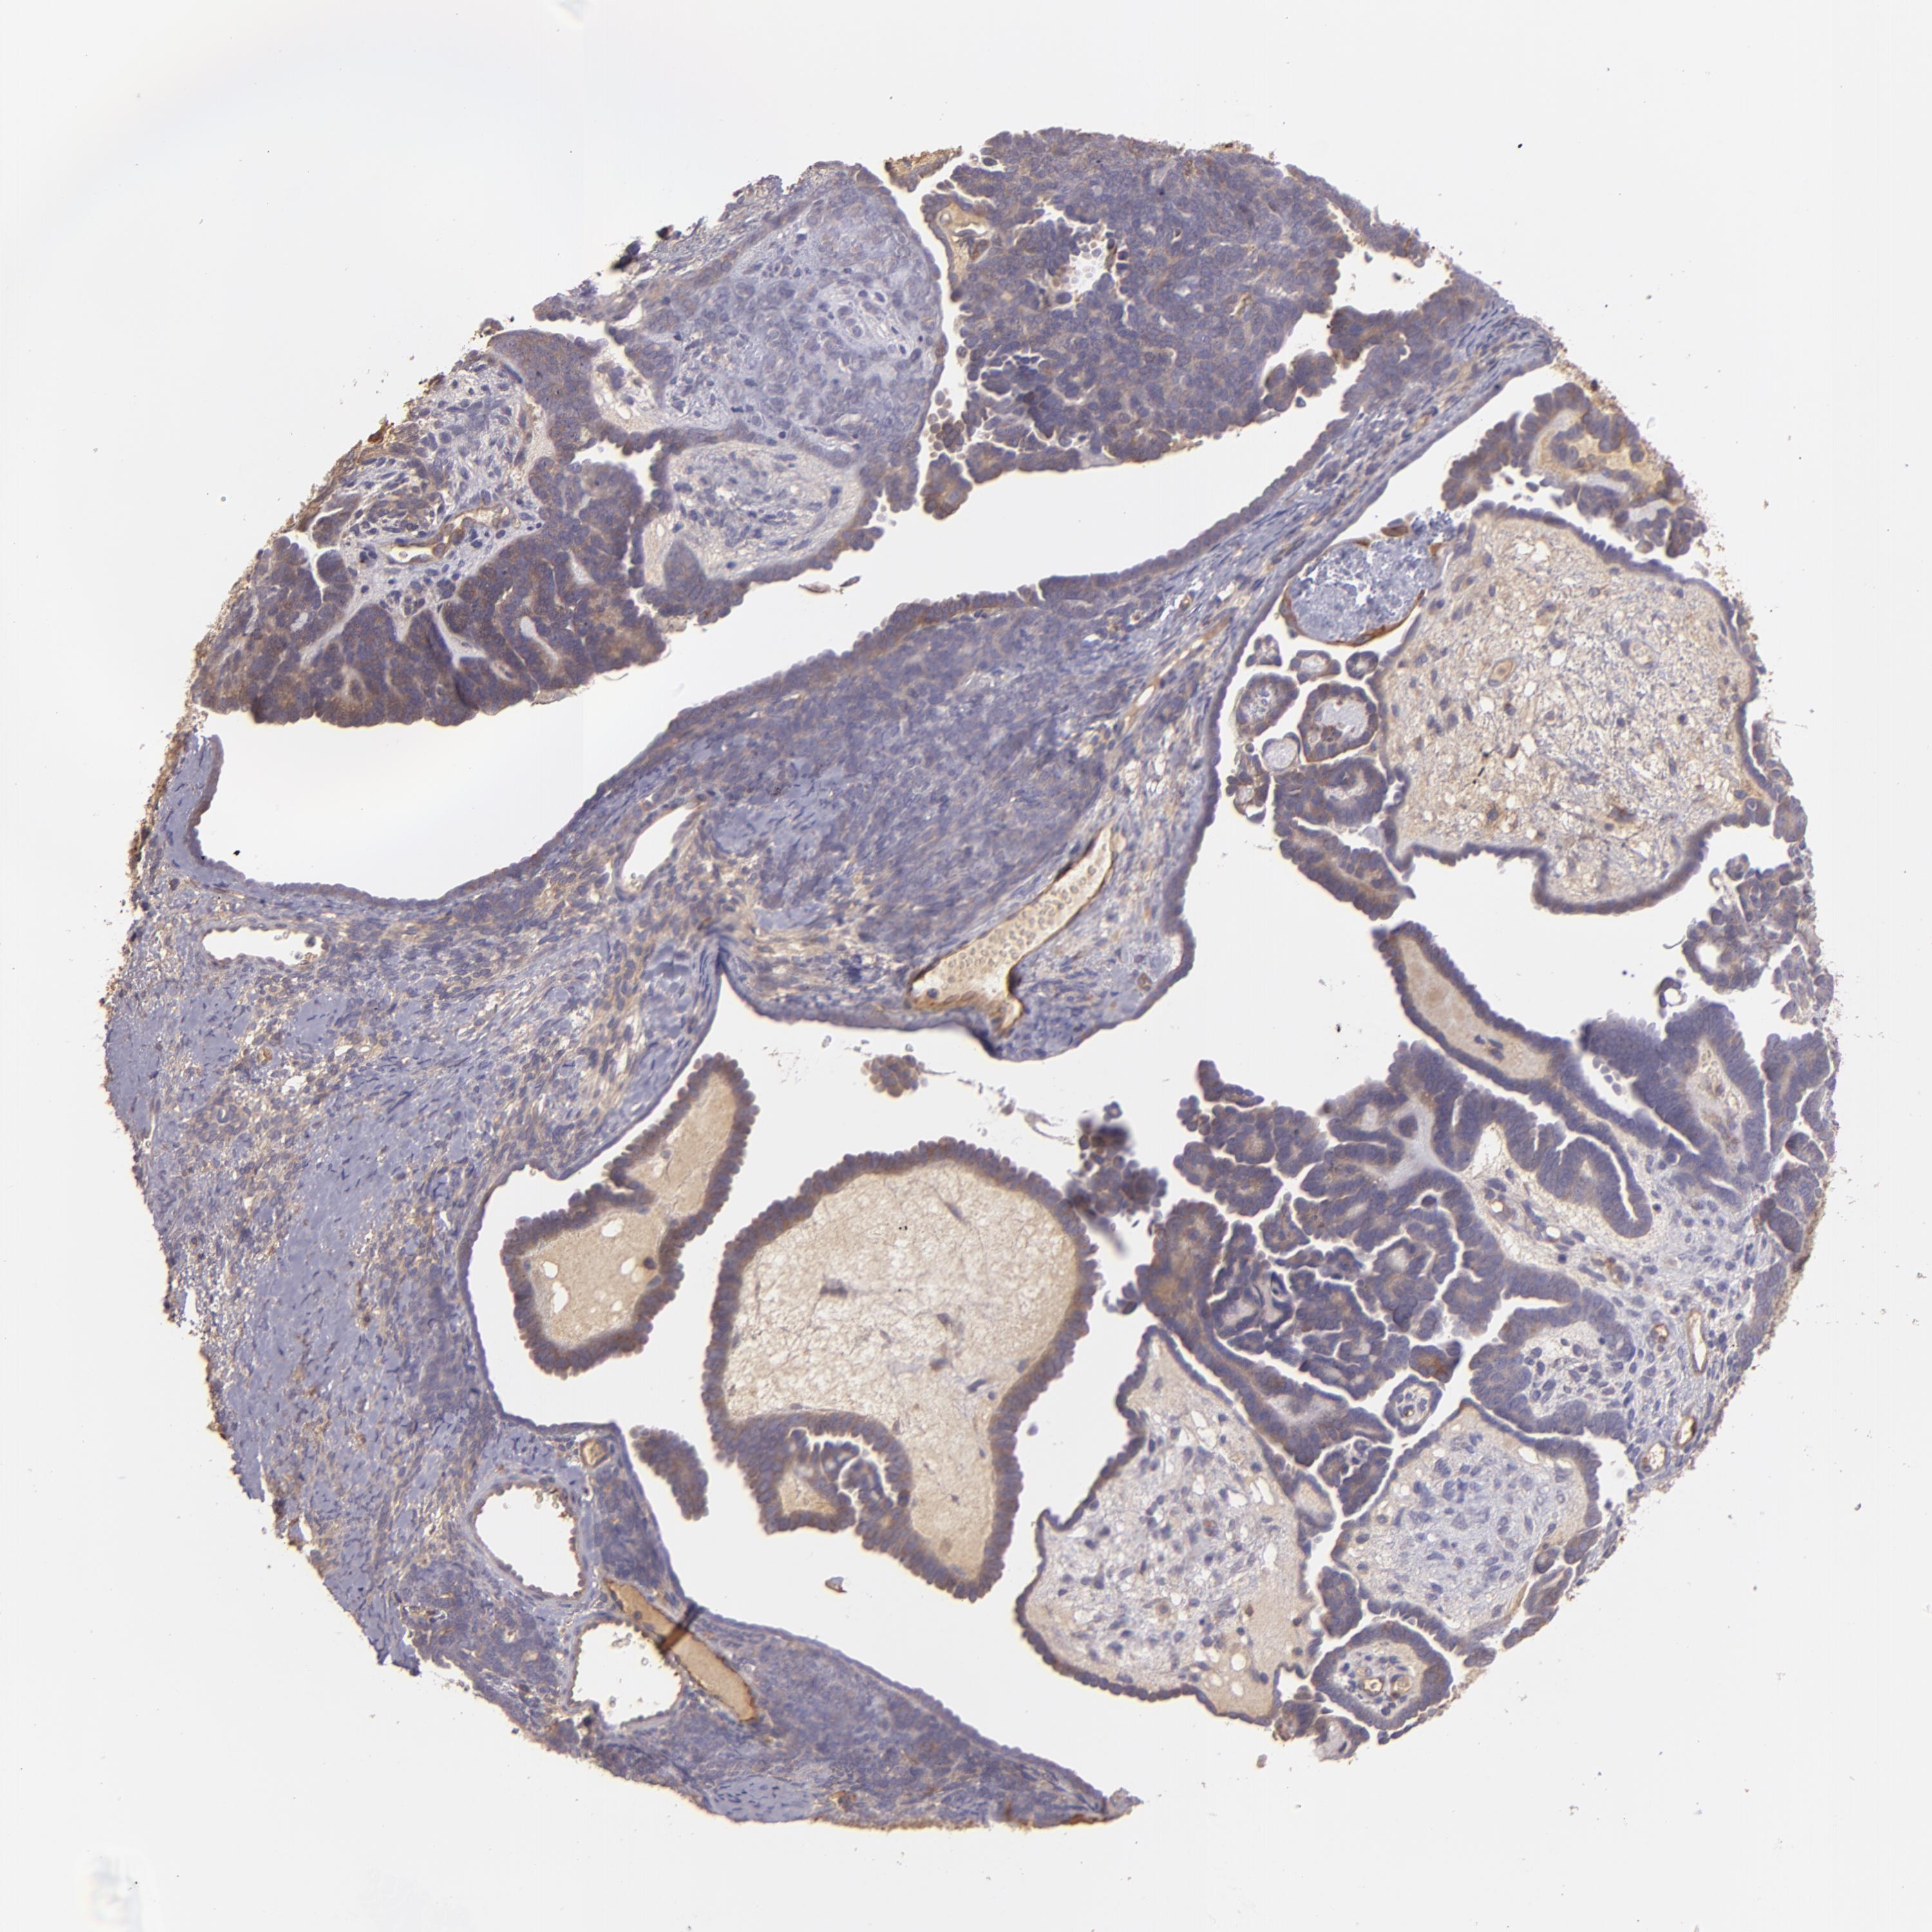

ENDOMETRIAL CANCER - Protein expressioni

A mouse-over function shows sample information and annotation data. Click on an image to view it in a full screen mode. Samples can be filtered based on level of antibody staining by selecting one or several of the following categories: high, medium, low and not detected. The assay and annotation is described here.

Note that samples used for immunohistochemistry by the Human Protein Atlas do not correspond to samples in the TCGA dataset.

Antibody stainingi

Antibody staining in the annotated cell types in the current human tissue is reported as not detected, low, medium, or high, based on conventional immunohistochemistry profiling in selected tissues. This score is based on the combination of the staining intensity and fraction of stained cells.

Each image is clickable and will lead to virtual microscopy that enables deeper exploration of all samples and also displays staining intensity scores, fraction scores and subcellular localization as well as patient and tissue information for each sample.

Antibody HPA001490

Antibody HPA013616

Staining

High

Medium

Low

Not detected

Intensity

Strong

Moderate

Weak

Negative

Quantity

>75%

75%-25%

<25%

None

Location

Nuclear

Cytoplasmic/membranous

Cytoplasmic/membranous,nuclear

Adenocarcinoma, NOS

Neoplasm, malignant, NOS